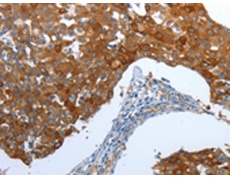

IHC positive control: |

Human breast cancer and Human thyroid cancer |

IHC Recommend dilution: |

25-100 |